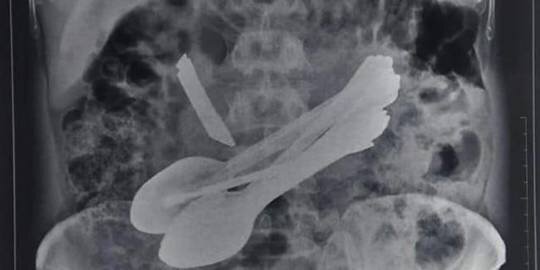

Xəstəxanadakı rentgen nəticələri xəstənin qarnında bir neçə yad maddənin olduğunu göstarib və bundan sonra təkrar əməliyyat olunan xəstənin qarnından 8 qaşıq, 2 vintaçan, 2 diş fırçası, bir mətbəx bıçağı və bir qapı kilidi çıxarılıb.